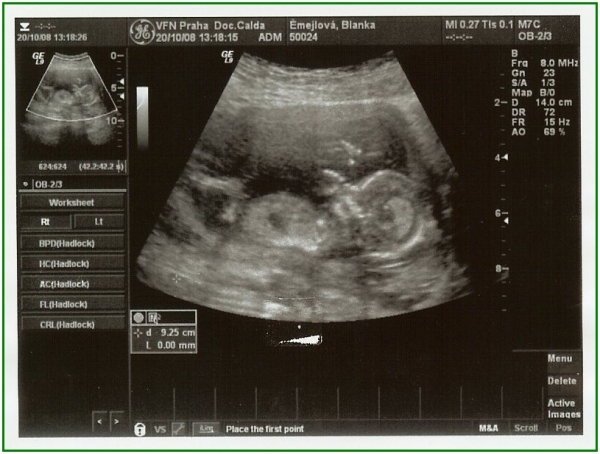

... další sledování aktivit. Lahvička se mrská jako blázen :-))) 15. dubna